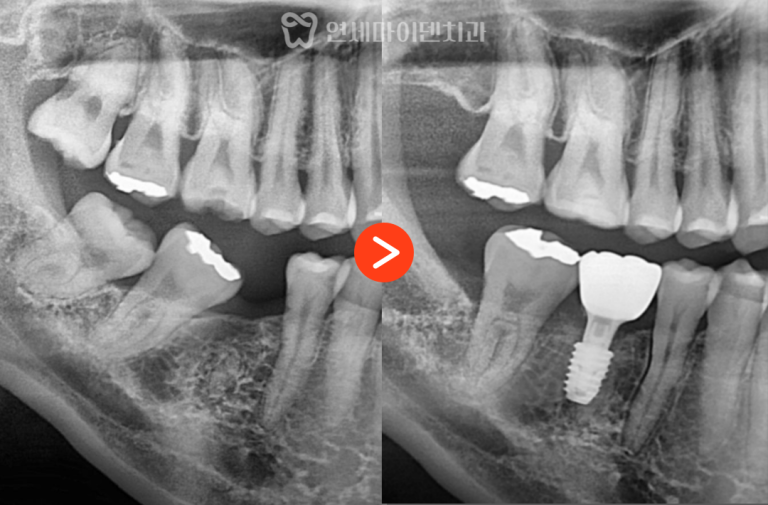

부분교정·임플란트 협진 증례: 쓰러진 어금니 “임플란트 해야 하는데치아가 쓰러져서 공간이 부족해요.” 임플란트를 계획하고 내원하신 분들 중의외로…